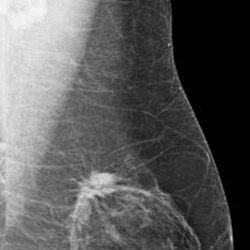

Risk-based screening misses breast cancers in women in their forties

A study of breast cancers detected with screening mammography found that strong family history and dense breast tissue were commonly absent in women between the ages of 40 and 49 diagnosed with breast cancer. Results of the study were presented today at the annual meeting of the Radiological Society of North America (RSNA). "Screening recommendations for this age group … [Read more...]